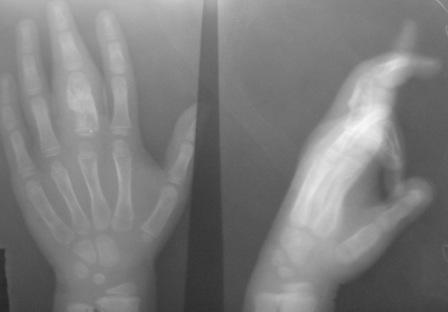

Уважаемые коллеги, на осмотре девочка 2006 г.рожд. Со слов матери 3мес. назад заметила припухлость основного фаланга 3-пальца, которая постепенно увеличилось до настоящего размера где-то в течении месяца, не болит, ребенка не беспокоит, признаки воспаления отсутствуют. Консультация онколога, биопсия - опухоль исключена (со слов матери), фтизиоортопед - тбс исключен. От основной фаланги 3 пальца к головке 4-пястной кости под кожей прощупывается хрящевидная ткань. Р-граммы от 10 декабря и 15 февраля, и фото прилагается. Что делать? Уважаемые коллеги, помогите! С уважением Абдурашид.

Уважаемый Игорь Владимирович! Я очень рад Вас услышать! И в самом деле это один из вариантов дисхондроплазии ( т.н. болезнь Оллье), так как принесли результат биопсии: -"эмбриональный хрящевой ткань, симулирующий хрящевую опухоль"

Планируем операцию экскохлеацию и выскабливанию с максимальным сохранением футляра из надкостницы и ростковую зону и тампонада с аутостружкой.

Конечно, мы во время операции будем брать материал на гистологию, а также удаление очага и замещение аутотрансплантатом тоже в плане рассматривается, как на примере, которая была представлена на форуме. правда снимки не очень качественные, прощу извинения!